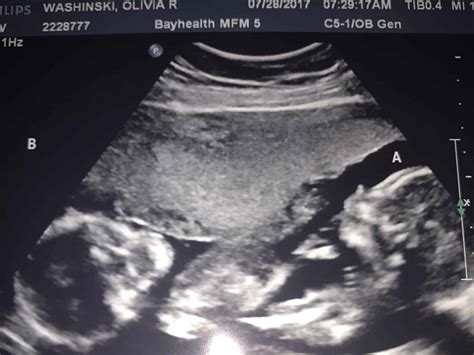

• Multiple Pregnancies: If you are carrying multiples, the scan may take longer, and additional assessments may be required.

• High-Risk Pregnancies: For high-risk pregnancies, additional scans and monitoring may be recommended.